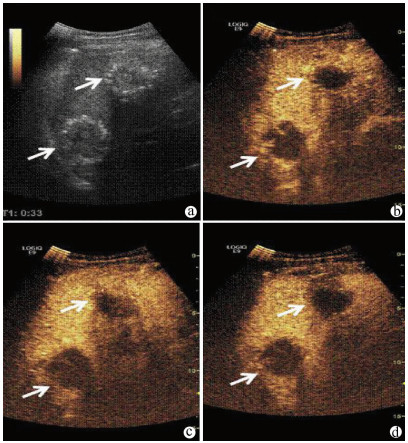

Guideline for ultrasonic diagnosis of liver diseases

Chinese Society of Ultrasound in Medicine, Oncology Intervention Committee of Chinese Research Hospital Society, National Health Commission Capacity Building and Continuing Education Expert Committee on Ultrasonic Diagnosis

2021, 37(8): 1770-1785. DOI: 10.3969/j.issn.1001-5256.2021.08.007

Abstract(3025) HTML (6526) PDF (9311KB)(794)

Abstract:

Ultrasound is a non-invasive, real-time, inexpensive, radiation-free and easily repeatable method, usually used for liver imaging. In recent years, new ultrasound examination techniques for liver diseases such as contrast-enhanced ultrasound and elastography have been rapidly developed, which can effectively identify intrahepatic space-occupying lesions, assess the degree of liver fibrosis and portal hypertension, and monitor the effects of treatment. Therefore, these technologies play an important diagnostic role in clinical liver diseases and have therapeutic interventional value. This guideline classifies the instrument set-up, patient preparation, and physician examination methods through multimodal ultrasound examinations (gray-scale ultrasound, color Doppler ultrasound, contrast-enhanced ultrasound, elastic ultrasound) for liver diseases. In addition, liver diseases multimodal ultrasound technology diagnostic criteria for diffuse hepatic lesions (inflammatory lesions, fibrosis, and sclerosis), multiple space-occupying lesions, and interventional procedures have been defined and standardized. Concurrently, we also recommend the ultrasound monitoring time interval and diagnostic report writing standard for liver diseases.